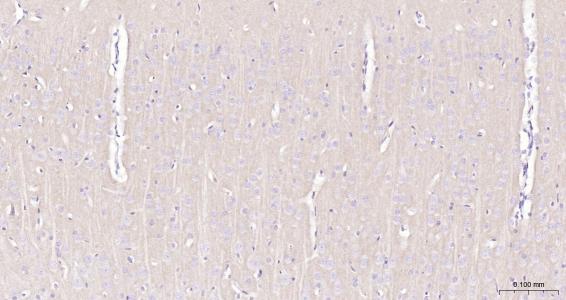

IHC-PHuman, Mouse, Rat1:50-200

组织特异性

Highly expressed in brain, especially in cerebral cortex, thalamus, hippocampus, frontal, occipital and temporal lobe, occipital pole and cerebellum, followed by corpus callosum, caudate nucleus, spinal cord, amygdala and medulla. Weakly expressed in heart, testis and skeletal muscle.